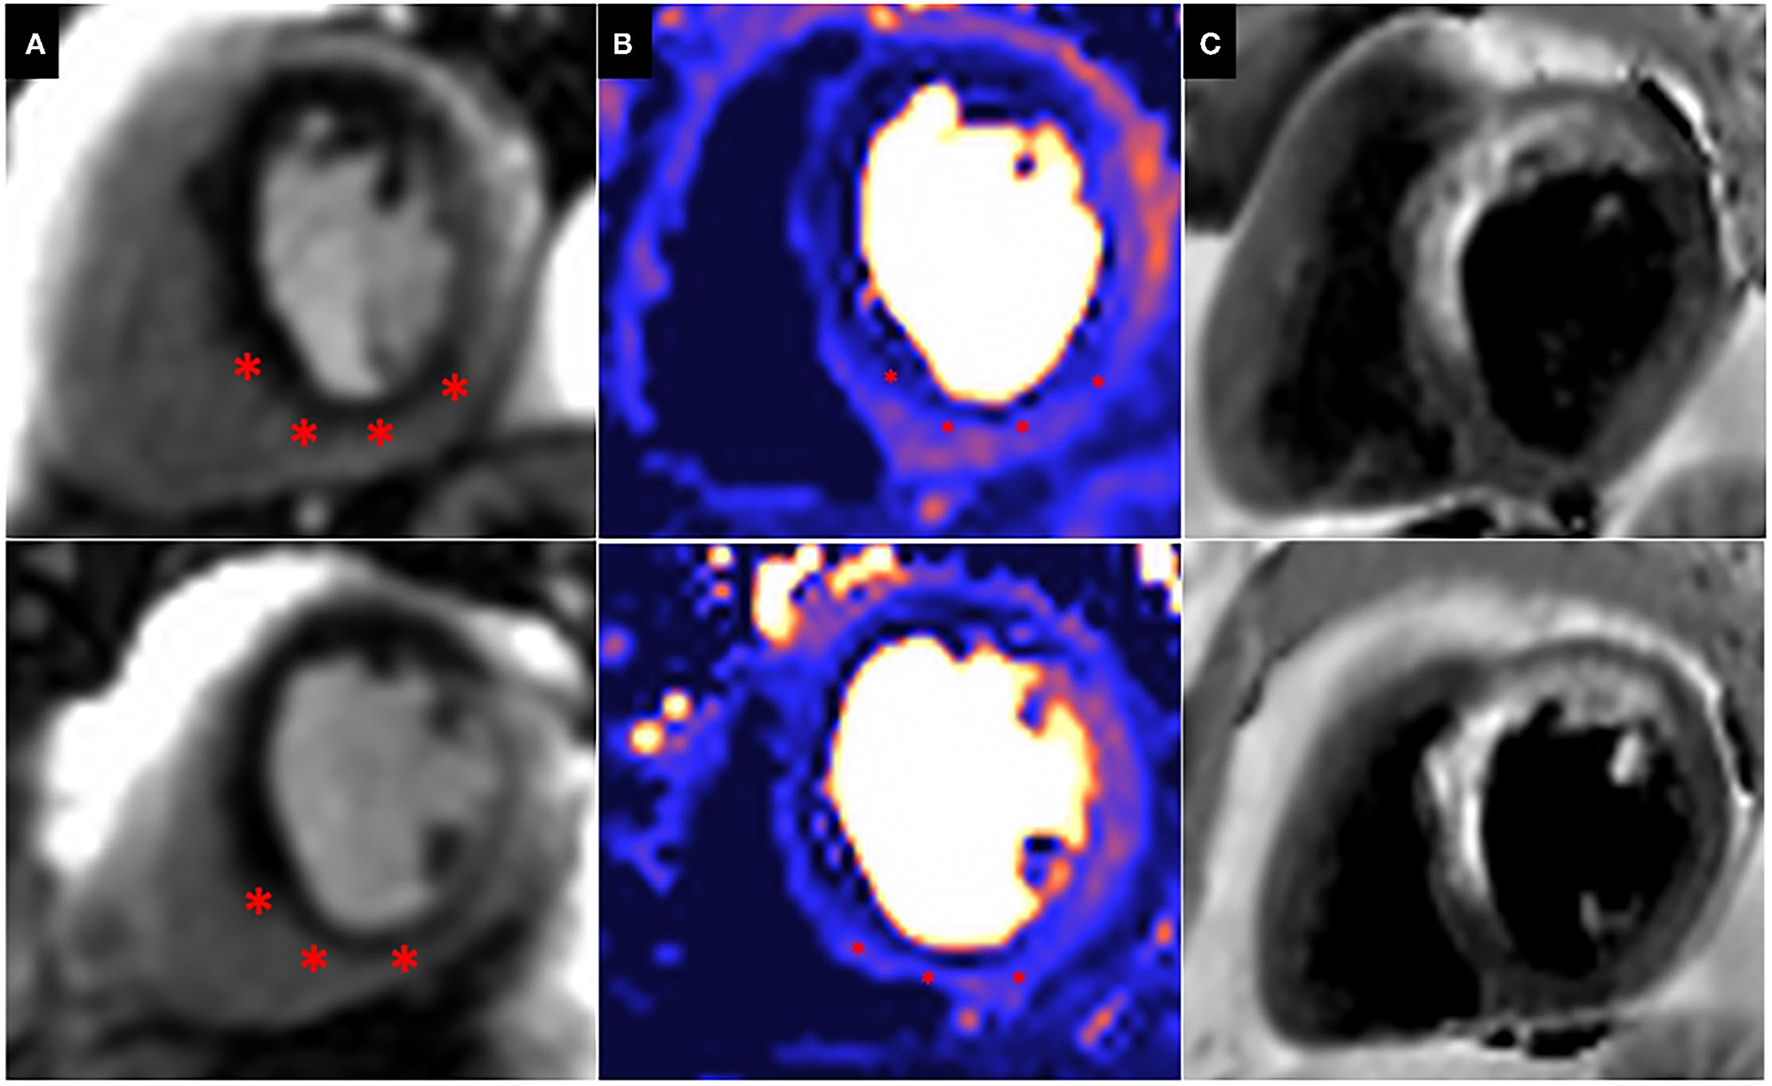

Patients with prior surgical revascularisation often have complex patterns of previous myocardial infarction with a number of studies demonstrating a wide range of scar pattern and distribution post procedure (55, 56). This indeed reflects the multi-factorial etiology of ischaemic injury sustained by these patients, including the impact of surgery itself. The presence of complex myocardial scar makes evaluation of ischaemia challenging, particularly when this is super-imposed or adjacent to areas of scar. Bernhardt et al., combined CMR perfusion and tissue characterization with late gadolinium enhancement (LGE) assessment and reported improved prediction of clinically relevant bypass graft stenosis, supporting the idea that ischaemia interpretation in patients post CABG requires some knowledge of scar distribution (57) (Figure 4).

Figure 4. Peri-infarct ischaemia and scar. Basal (top) and Mid (Bottom) short axis views of a CMR perfusion in patient scheduled to undergo coronary artery bypass graft surgery, demonstrating a previous infarct within the left anterior descending (LAD) territory and a large superimposed perfusion defect extending beyond the area of previous infarction (*). (A) First pass perfusion CMR during adenosine stress; (B) Perfusion mapping of the same myocardial segment as shown in (A). (C) Dark blood LGE demonstrating a previous infarction within the LAD territory.